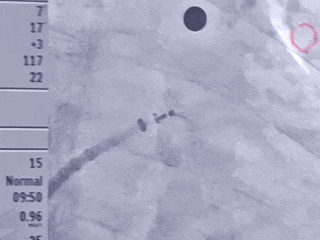

牵拉试验

调整封堵器后牵拉封堵器确认封堵器稳定

再次造影

封堵器稳定封堵,无残余分流